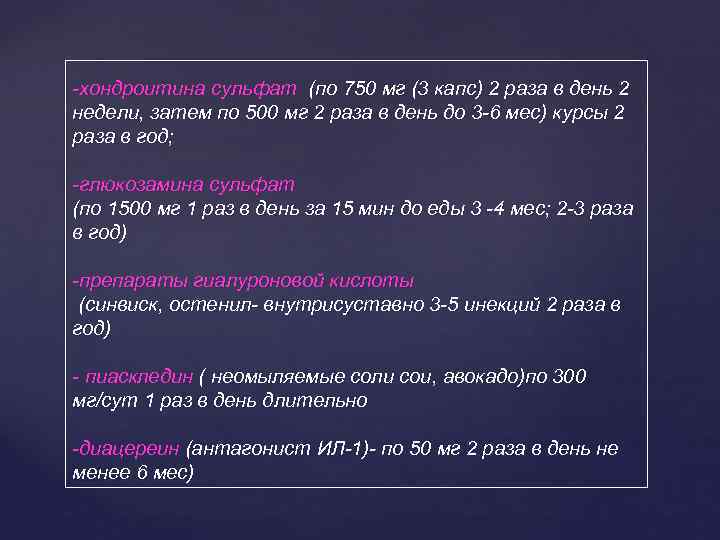

-хондроитина сульфат (по 750 мг (3 капс) 2 раза в день 2 недели, затем по 500 мг 2 раза в день до 3 -6 мес) курсы 2 раза в год; -глюкозамина сульфат (по 1500 мг 1 раз в день за 15 мин до еды 3 -4 мес; 2 -3 раза в год) -препараты гиалуроновой кислоты (синвиск, остенил- внутрисуставно 3 -5 инекций 2 раза в год) - пиаскледин ( неомыляемые соли сои, авокадо)по 300 мг/сут 1 раз в день длительно -диацереин (антагонист ИЛ-1)- по 50 мг 2 раза в день не менее 6 мес)

-хондроитина сульфат (по 750 мг (3 капс) 2 раза в день 2 недели, затем по 500 мг 2 раза в день до 3 -6 мес) курсы 2 раза в год; -глюкозамина сульфат (по 1500 мг 1 раз в день за 15 мин до еды 3 -4 мес; 2 -3 раза в год) -препараты гиалуроновой кислоты (синвиск, остенил- внутрисуставно 3 -5 инекций 2 раза в год) - пиаскледин ( неомыляемые соли сои, авокадо)по 300 мг/сут 1 раз в день длительно -диацереин (антагонист ИЛ-1)- по 50 мг 2 раза в день не менее 6 мес)